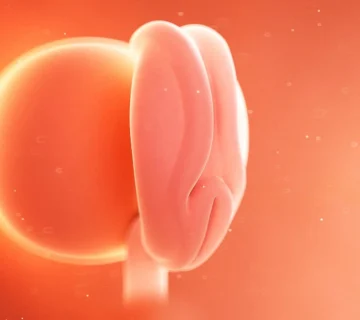

🧬 اتفاقات درون نوزاد در هفته دوازدهم بارداری

در هفته دوازدهم بارداری، نوزاد شما تقریباً به اندازهی یک لیموترش کوچک است — حدود ۷ سانتیمتر طول و حدود ۱۵ گرم وزن دارد. او حالا دیگر شبیه یک انسان واقعی است و در حال تمرین نفس کشیدن، بلعیدن و حتی سکسکه کردن است!

چهرهی جنین در این هفته شکل واضحتری گرفته است.

– سر او که پیشتر نصف طول بدنش بود، اکنون فقط یکسوم بدنش را تشکیل میدهد.

– پلکها، بینی، لب بالا و گوشها کاملاً شکل گرفتهاند.

– حرکات ظریف دستها و پاها شروع شدهاند، هرچند هنوز شما آنها را احساس نمیکنید.

درون بدن کوچک او، اتفاقات مهمی در حال رخ دادن است:

– خون در بند ناف جریان دارد و اکسیژن و مواد مغذی را از طریق جفت به جنین میرساند.

– کلیهها فعال شدهاند و ادرار تولید میکنند.

– سیستم عصبی در حال بلوغ است و عضلات به سیگنالهای مغزی پاسخ میدهند.